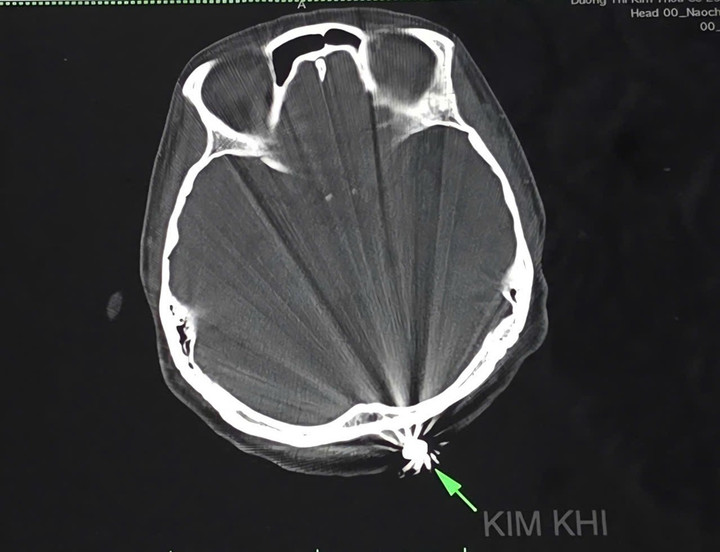

Hình ảnh tổn thương trên phim chụp. (Ảnh: BVCC)

Ca mổ kéo dài 45 phút, các bác sĩ mở rộng vết thương khoảng 3cm và lấy ra dị vật kim loại hình đầu đạn, kích thước 0,5x0,3cm. Đầu đạn xuyên qua lớp da, chạm nhẹ xương chẩm, không gây tổn thương nghiêm trọng đến não hay các cấu trúc lân cận. Hiện bệnh nhân tỉnh táo, tiếp xúc tốt, vết mổ khô, không có dấu hiệu thần kinh bất thường.